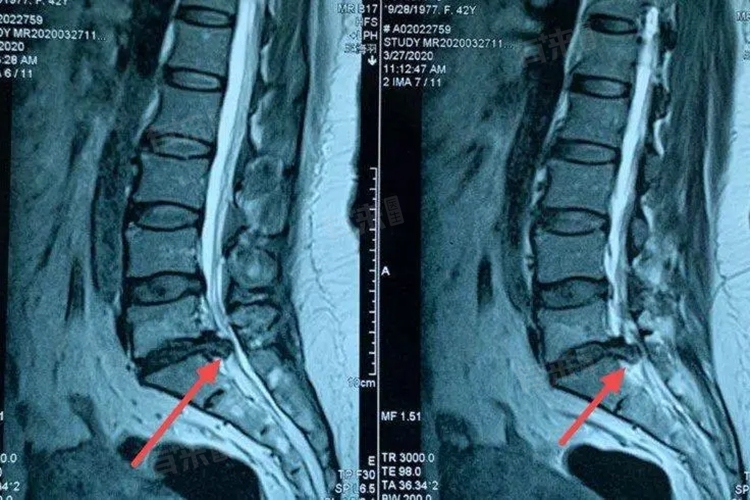

L4/5、L5/S1椎间盘膨出可能会导致腰部疼痛、下肢放射性疼痛、麻木、无力等症状,严重影响患者的生活质量。如果出现相关症状,应及时就医,通过影像学检查(如腰椎CT、磁共振成像等)明确诊断,并采取相应的治疗措施。